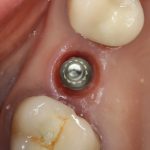

Их можно установить в минимально возможный объем костной ткани, где установка обычных взрослых имплантов невозможна без предварительной остеопластики. В некоторых случаях они даже позволяют избежать синуслифтинга, что, согласитесь, звучит очень заманчиво.

Другими словами, уважаемые друзья, ультракороткие импланты призваны сделать нашу работу проще. Мы реально получаем шанс избежать сложной остеопластики, в некоторых случаях — открытого синуслифтинга, которым любят пугать некоторые фанаты с ультракороткими писюнами.

Вот почему, дорогие друзья, я рассматривал, рассматриваю и буду рассматривать ультракороткие имплантаты, исключительно как компромиссное решение. Их использование — это, безусловно, план B или даже план C, но никак не основной и главный план имплантологического лечения. Ну и, говоря о компромиссе, мы должны понимать, что это всегда чревато какими-то минусами, которые, возможно, на первый взгляд не слишком заметны. Причём, это знаю не только я. Это знает всё мировое имплантологическое сообщество, это известно и компаниям-производителям — именно поэтому ультракороткие импланты занимают ту нишу, которую занимают, и не получают, к счастью, широкого распространения.

Однако, я должен еще раз подчеркнуть — я не против ультракоротких имплантов, не считаю, что они какие-то плохие, и недостойны называться имплантами. Но, как и в случае с базальной имплантацией, я склонен полагать, что они имеют весьма ограниченные показания к использованию, и ставить их всем подряд, без учета ряда факторов (в первую очередь, протетики и качества жизни пациентов) — не хорошо и не правильно. Тем более, нельзя впаривать эти импланты, пугая пациента «страшной остеопластикой» или «ужасным синуслифтингом«. Другое дело, что в практике случаются ситуации, когда по каким-то причинам мы просто НЕ МОЖЕМ провести наращивание костной ткани, и вот в таких случаях ультракороткие импланты — самое отличное решение.